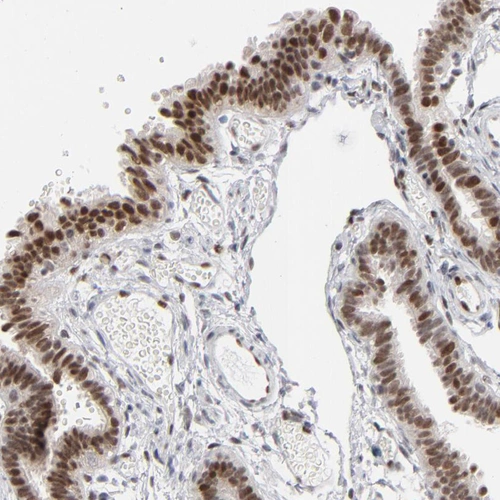

Immunohistochemical staining of human lymph node shows moderate nuclear positivity in non-germinal center cells.